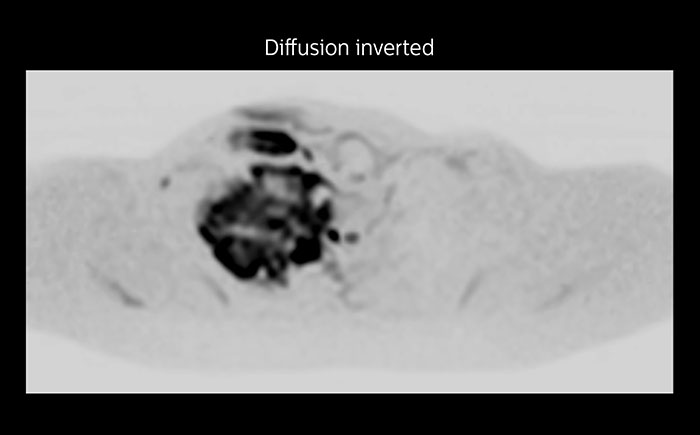

MRI of Pancoast tumor

Although the area between the neck and the top of the lung is one of the most difficult areas for MRI, Prodiva 1.5T images show good quality in this 56-year-old male with Pancoast tumor on the right. mDIXON TFE images shows excellent fat suppression in the neck area and the DWI shows almost no distortion.

MRI of Pancoast tumor

Although the area between the neck and the top of the lung is one of the most difficult areas for MRI, Prodiva 1.5T images show good quality in this 56-year-old male with Pancoast tumor on the right. mDIXON TFE images shows excellent fat suppression in the neck area and the DWI shows almost no distortion.